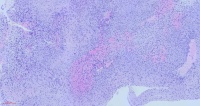

鼻咽肿物

性别年龄59岁临床诊断鼻咽肿物真菌性鼻窦炎

一般病史CT:双侧咽隐窝及咽鼓管开口无变窄,咽鼓管隆突未见增厚,双侧咽旁间隙清晰。左上颌窦内见结节状软组密度影,大小约3.7cm×3.7cm,增强扫扫描呈欠均匀强化,邻近左上颌窦壁见骨质吸收、破坏,部分骨质增厚且密度增高呈骨质硬化改变;左上颌窦内软组织密度影,考虑低度恶性肿瘤与真菌性鼻窦炎鉴别,建议活检;

标本名称鼻腔病损

大体所见灰黄碎组织,质中

免疫组化结果: MDM2(-),CDK4(-),Ki67约60%(+),CD34(-),S100(-),SATB2(+),SMA(-),Desmin(-),P40(上皮+),EGFR(上皮+),CK(上皮+),EMA(上皮+),Vimentin(+)。

癌,没问题。

考虑:鼻咽癌(鳞癌)

鳞癌,非角化型。